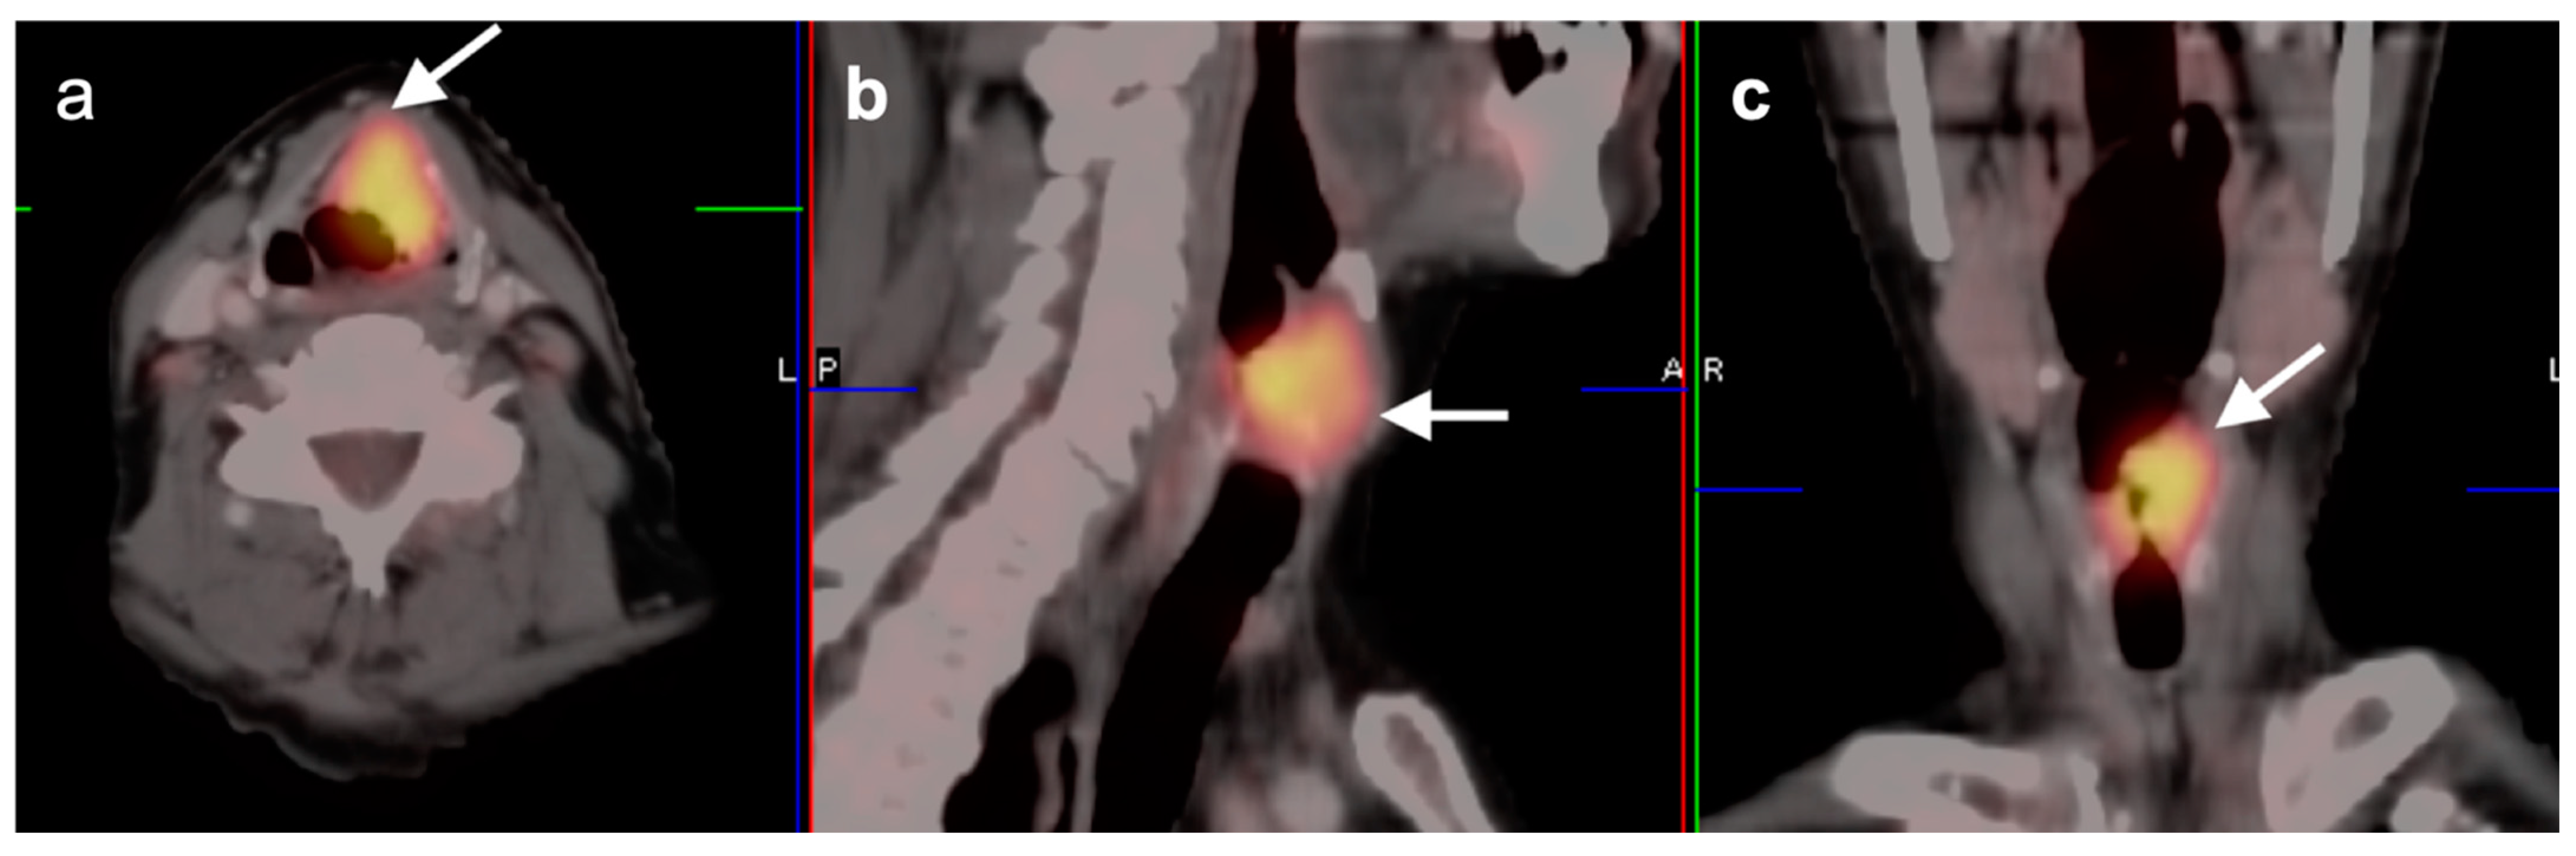

2.2. Squamous Cell Carcinoma of the Head and Neck (SCCHN)

2.3. Nasopharyngeal Carcinoma

2.6. Thyroid Cancer

- Medullary thyroid cancer